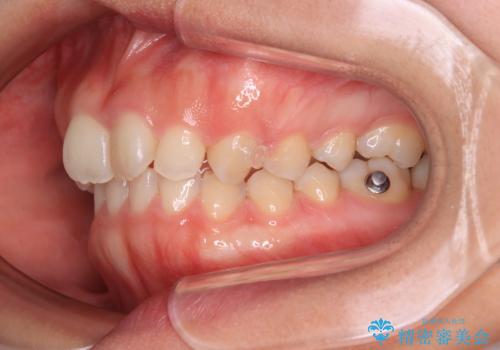

- 上の前歯が前方に飛び出していることを気にして来院された患者様です。

奥歯の咬み合わせをチェックすると、上顎歯列が相対的に前方に位置しているため、補助装置を用いて上顎歯列を確実に後方に移動させ、インビザラインで歯列を整えて行くこととしました。

インビザライン単体でも同様の結果が得られる可能性がありますが、万が一奥歯がうまく後方移動できなかった場合、リカバリーが非常に大変となるため、事前に補助装置を併用して確実に結果が得られるように工夫をしています。